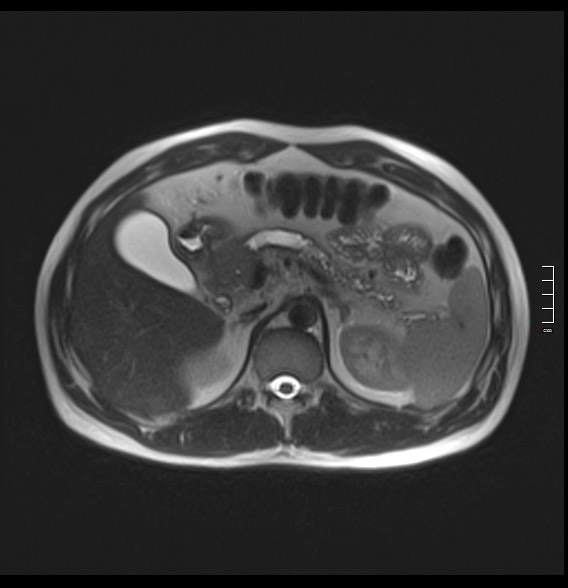

2910. Расширение панкреатического протока очевидно было вызвано